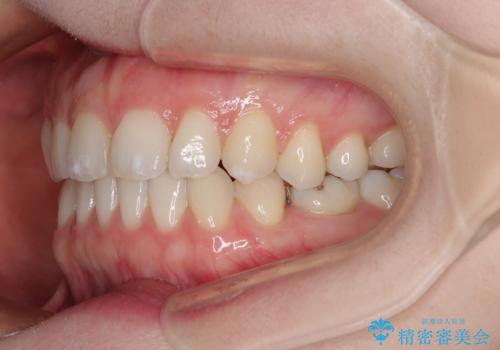

すきっ歯をインビザラインできれいな歯並びに改善

- 前歯の隙間を気にして来院された患者様です。

隙間や叢生の程度はそれほど著しいものではなかったので、インビザラインでもワイヤー矯正でも対応可能でしたが、極力目立たない装置を希望されたため、インビザラインにて矯正治療を行うこととしました。